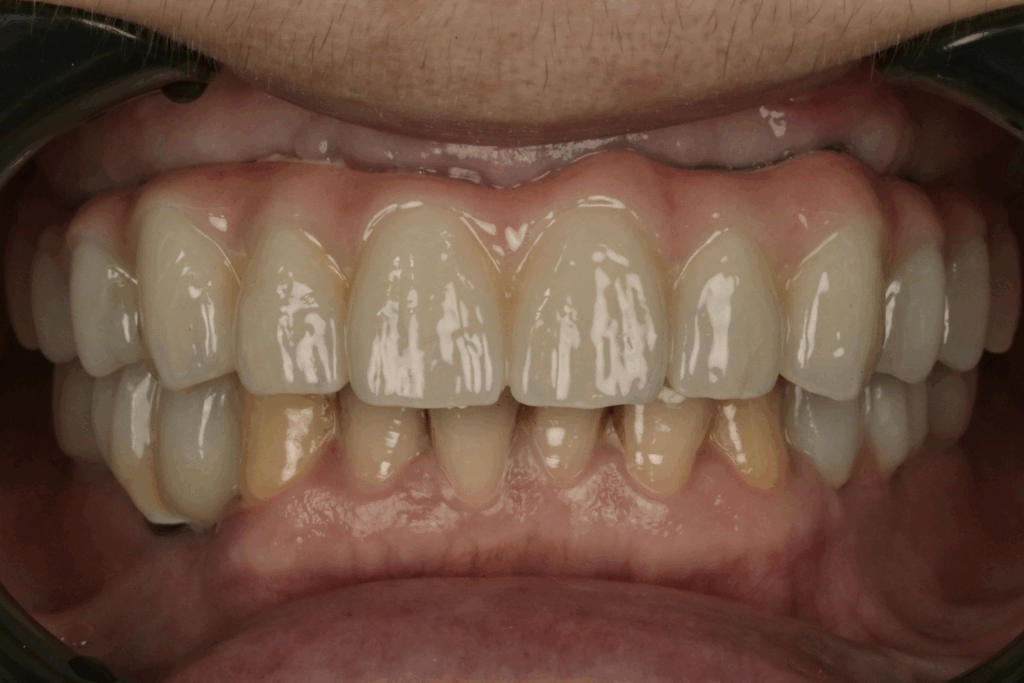

案例2. 上顎+下顎All on X

Before

After